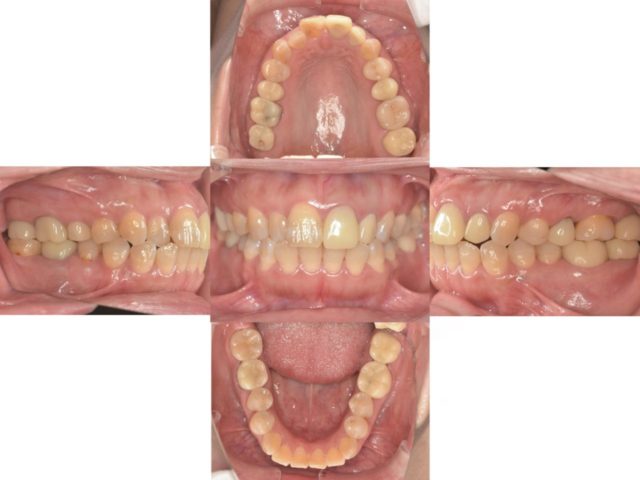

こちらの患者様は最終のセラミックスまで装着が終了しました。

経過観察中に他にも治療が必要な歯があったので同時進行で治療を行いました。

現在の口腔内写真がこちらです!

初診時から比べるととても綺麗になりました

患者様も快適にお食事できる、見た目も綺麗になったととても満足していただいてます!